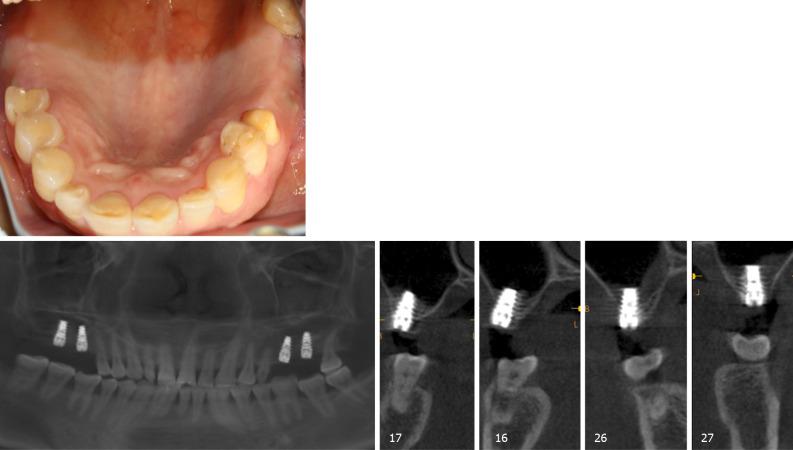

A 65-year-old female with no contraindications for dental implants and loss of maxillary bilateral molars is described. Examination by CBCT showed the available vertical bone height in the bilateral posterior maxilla was 0.5-6.8 mm in the left and 2.8-6.5 mm in the right. The patient underwent a transalveolar approach using platelet-rich fibrin and bone substitute with simulataneous placement of an implant 10 mm in length. Six months post-surgery, the implant showed excellent osseointegration with the bone graft. Thereafter, full-ceramic crowns were fitted. Follow-up at 2 years demonstrated satisfactory prognosis.

描述了一名65岁女性,无牙种植禁忌证且上颌双侧磨牙缺失。CBCT检查显示双侧上颌后牙区可用垂直骨高度左侧为0.5 - 6.8毫米,右侧为2.8 - 6.5毫米。患者接受了使用富含血小板纤维蛋白和骨替代物的经牙槽嵴入路,并同时植入了一枚10毫米长的种植体。术后6个月,种植体与骨移植材料显示出良好的骨结合。此后,安装了全瓷冠。2年的随访显示预后良好。